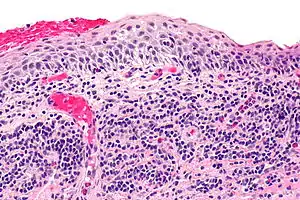

Micrograph of plasmacytosis mucosae. H&E stain.

Balanitis plasmacellularis is a skin condition characterized by a benign inflammatory skin lesion characterized histologically by a plasma cell infiltrate.[1][2]:657[3]